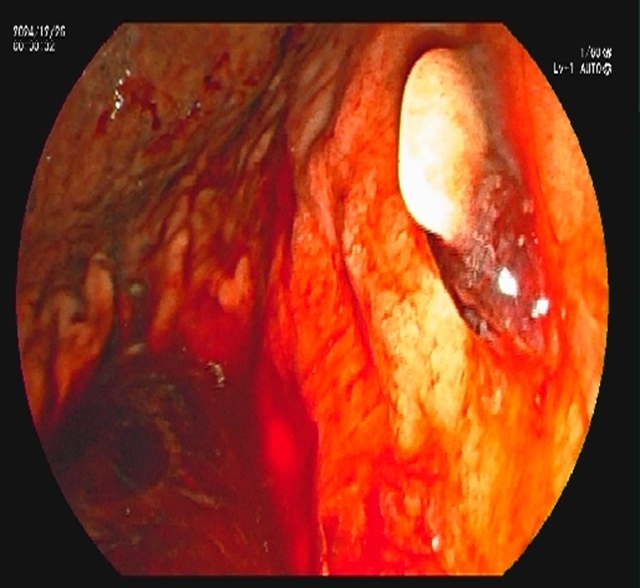

术后,放置鼻胆管持续引流脓性胆汁(当天引出300ml浑浊胆汁)。

4.一举多得:引流+诊断同步完成

内镜逆行胰胆管造影不仅能取石,还能通过鼻胆管持续引流脓性胆汁(每天引出200-500ml),快速降低胆道压力;同时,术中可采集胆汁送细菌培养,指导后续抗生素使用,实现"边治疗边诊断"。